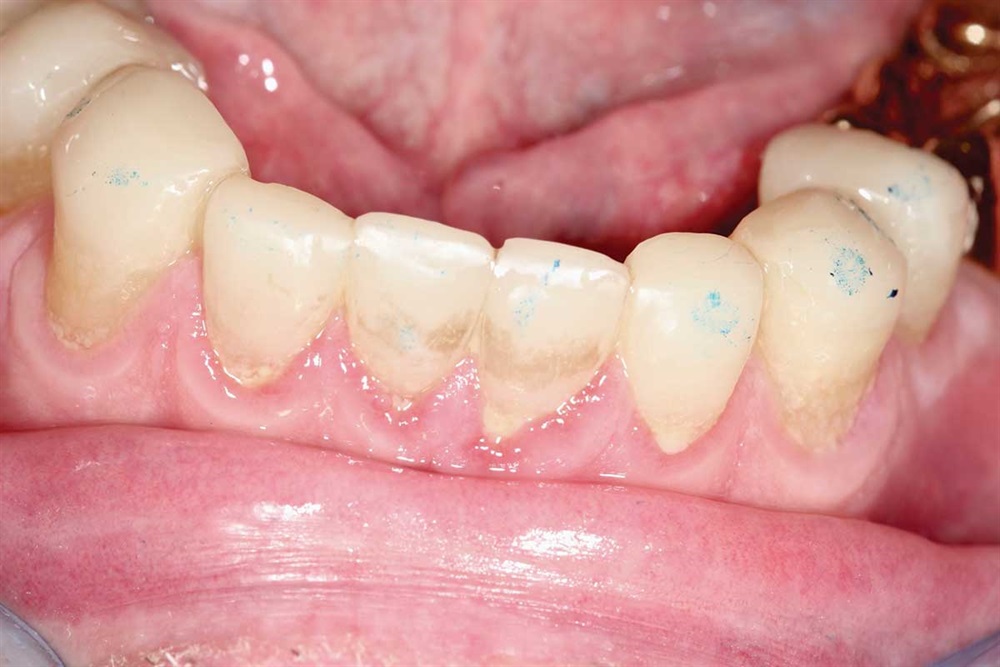

Fig. 3: Lower incisors. The patient’s dentists in Ontario wanted to do ortho for 18–24 months and then restorative crowns with many elective root canals, to the tune of a nice luxury car.